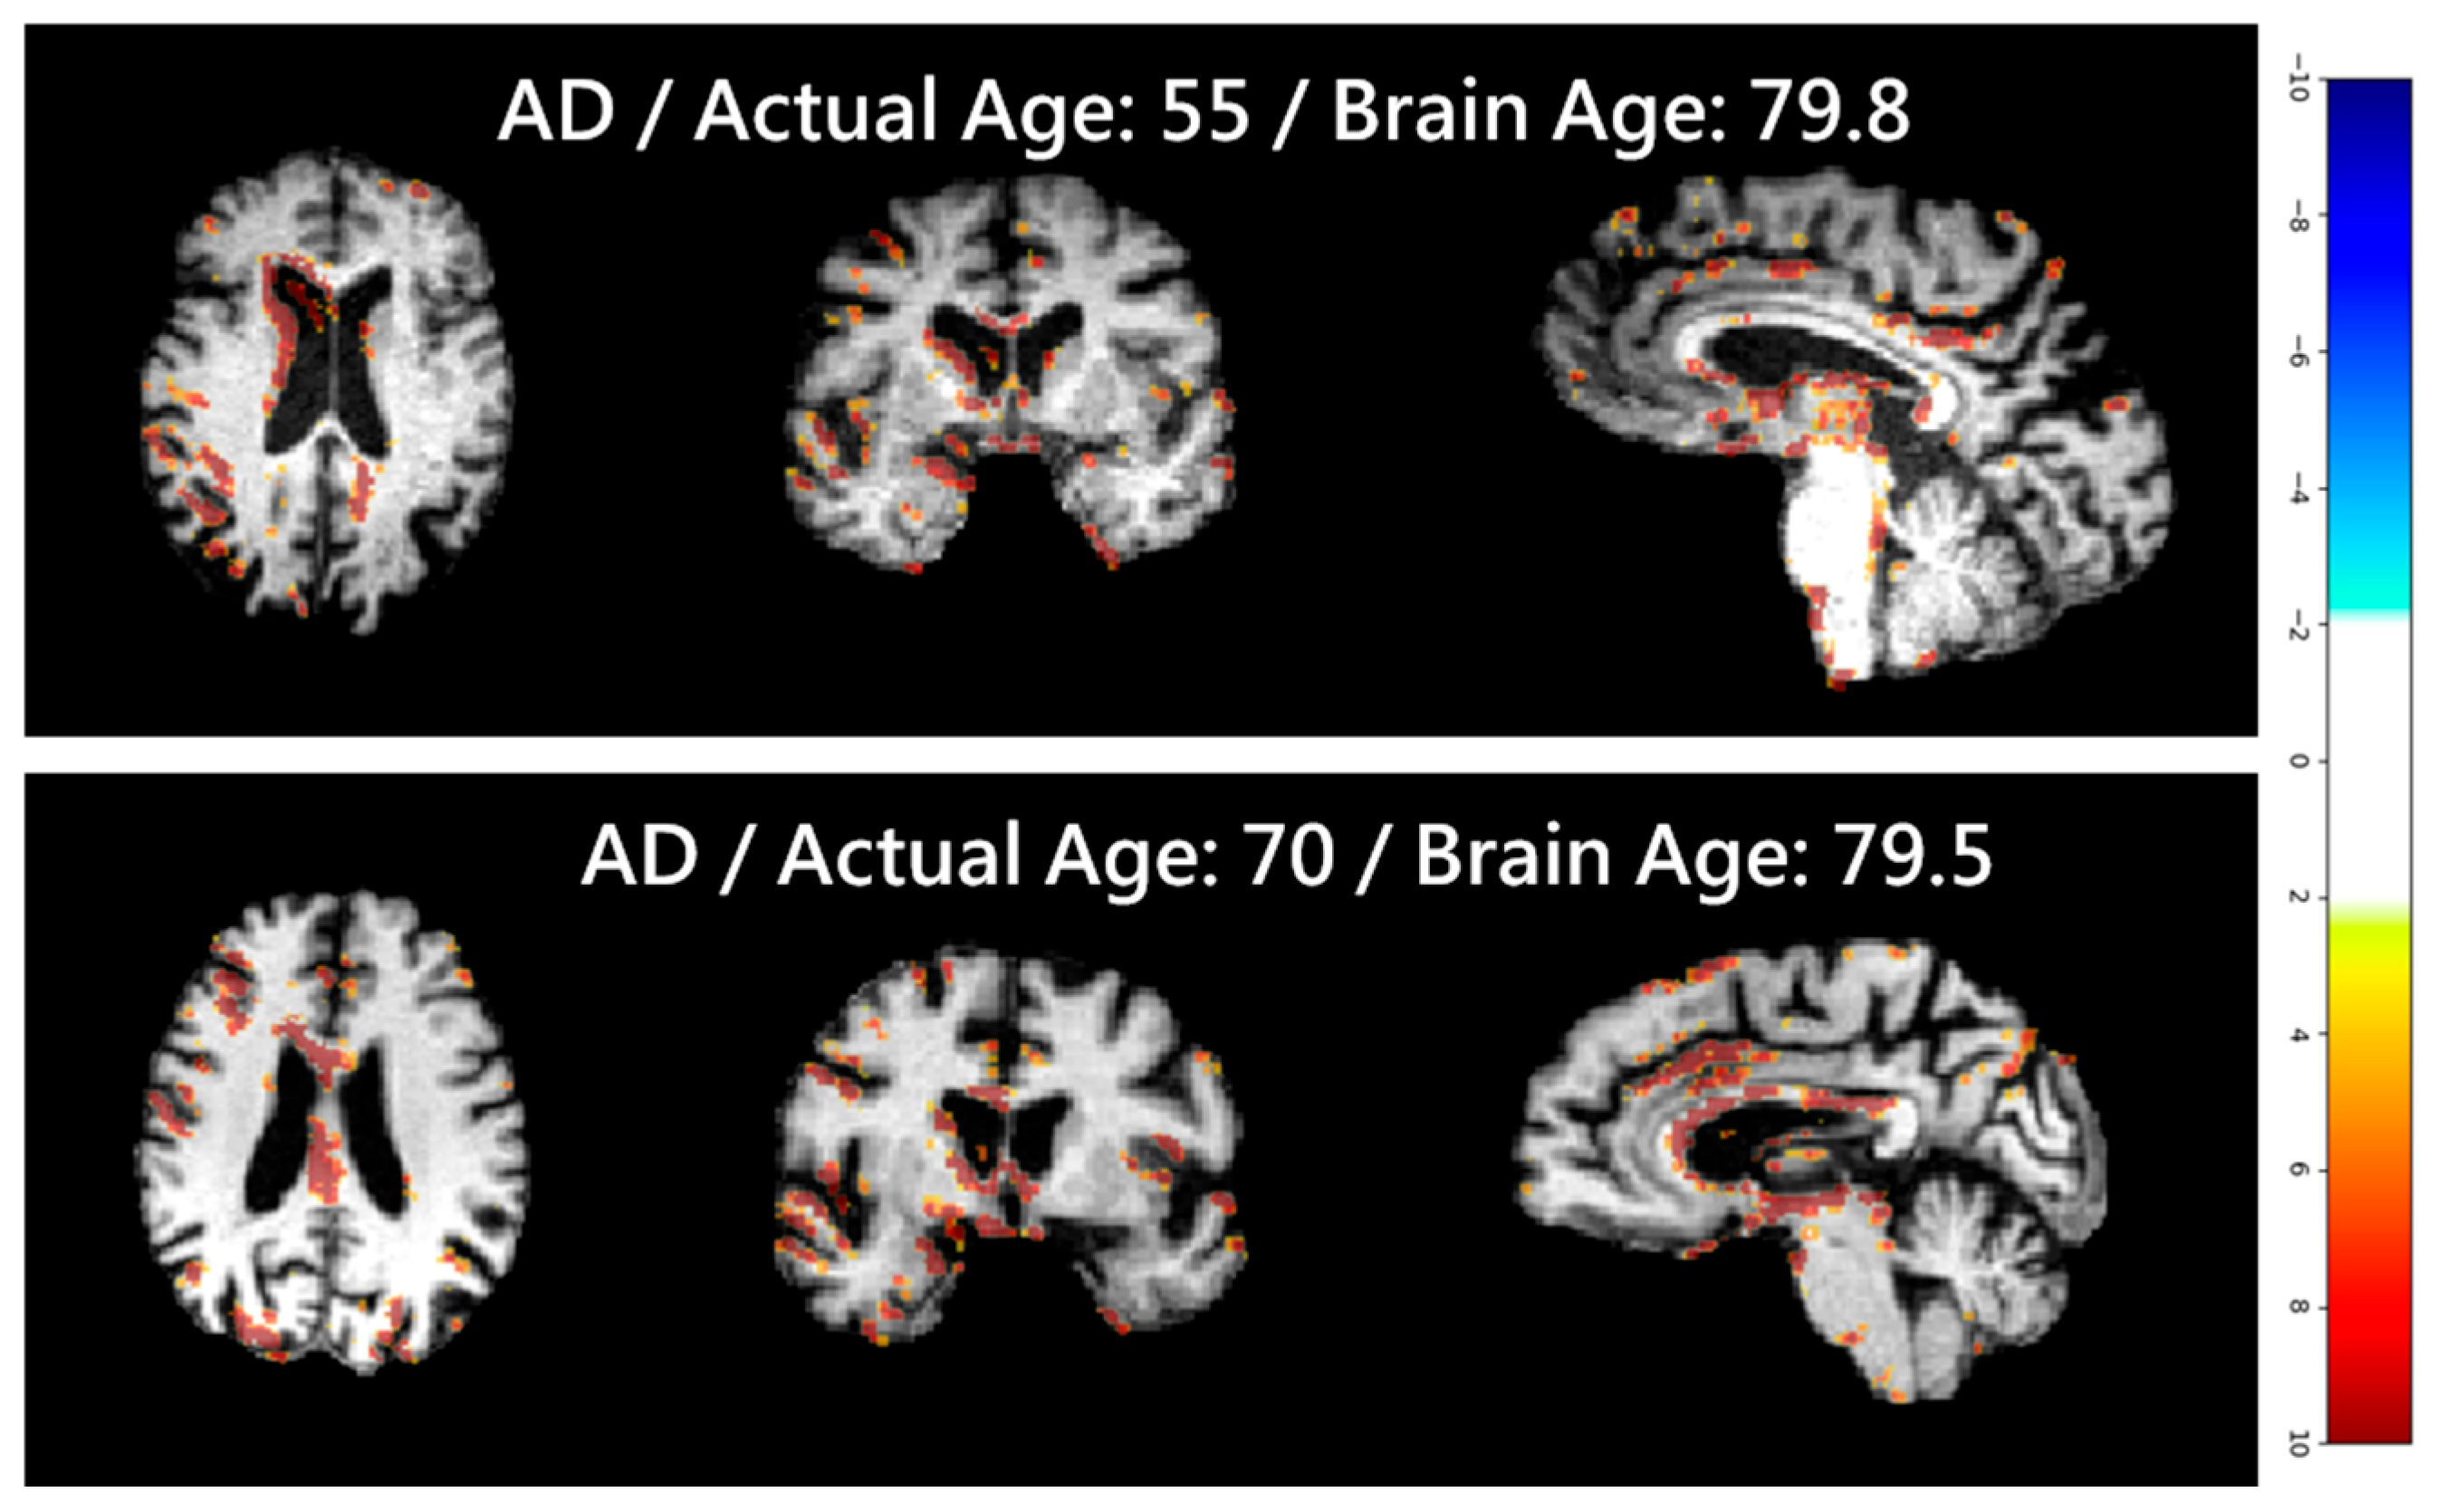

4.6. Softmax-Derived Brain Age Mapping Analysis